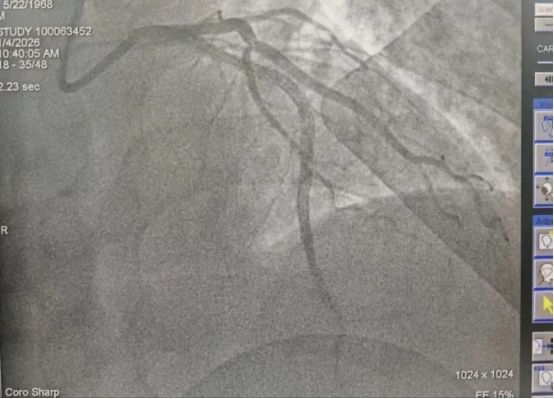

在120急救车医护人员的密切监护转运下,患者顺利转入西安市第九医院手术室,西安市第九医院介入医师团队提前做好术前准备,接到患者后立即为患者进行冠状动脉造影,PCI术中显示:“前降支闭塞”,成功植入支架一枚,堵塞的血管得以重新通畅,送患者至西安市第九医院,120急救车9:43到达该院大门时心内科会诊医生已提前在大门口等待,到院后绕行急诊科、CCU,第一时间直达介入导管室,心内介入手术团队接到患者后立即为患者进行急诊冠脉造影显示:冠脉多支多段重度病变,LAD近端完全闭塞,10:16导丝顺利通过,药物支架1枚干预LAD近端病变,D2W时间33分钟。

图为患者介入手术前后的心脏造影